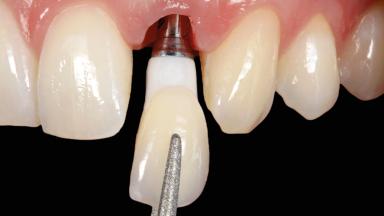

Immediate Implant Placement and Immediate Provisionalization with a Prefabricated-Shell Provisional Crown

In this case, Arndt Happe describes how he achieved a stable outcome at 5 years by giving careful attention to the coronal aspect of the transmucosal area of the provisional, creating a slim emergence profile.

Biological Screw-retained restorations with appropriate contours

Loading Protocol Immediate

Implant-supported provisional restoration Required, elevated esthetic and/or functional demands